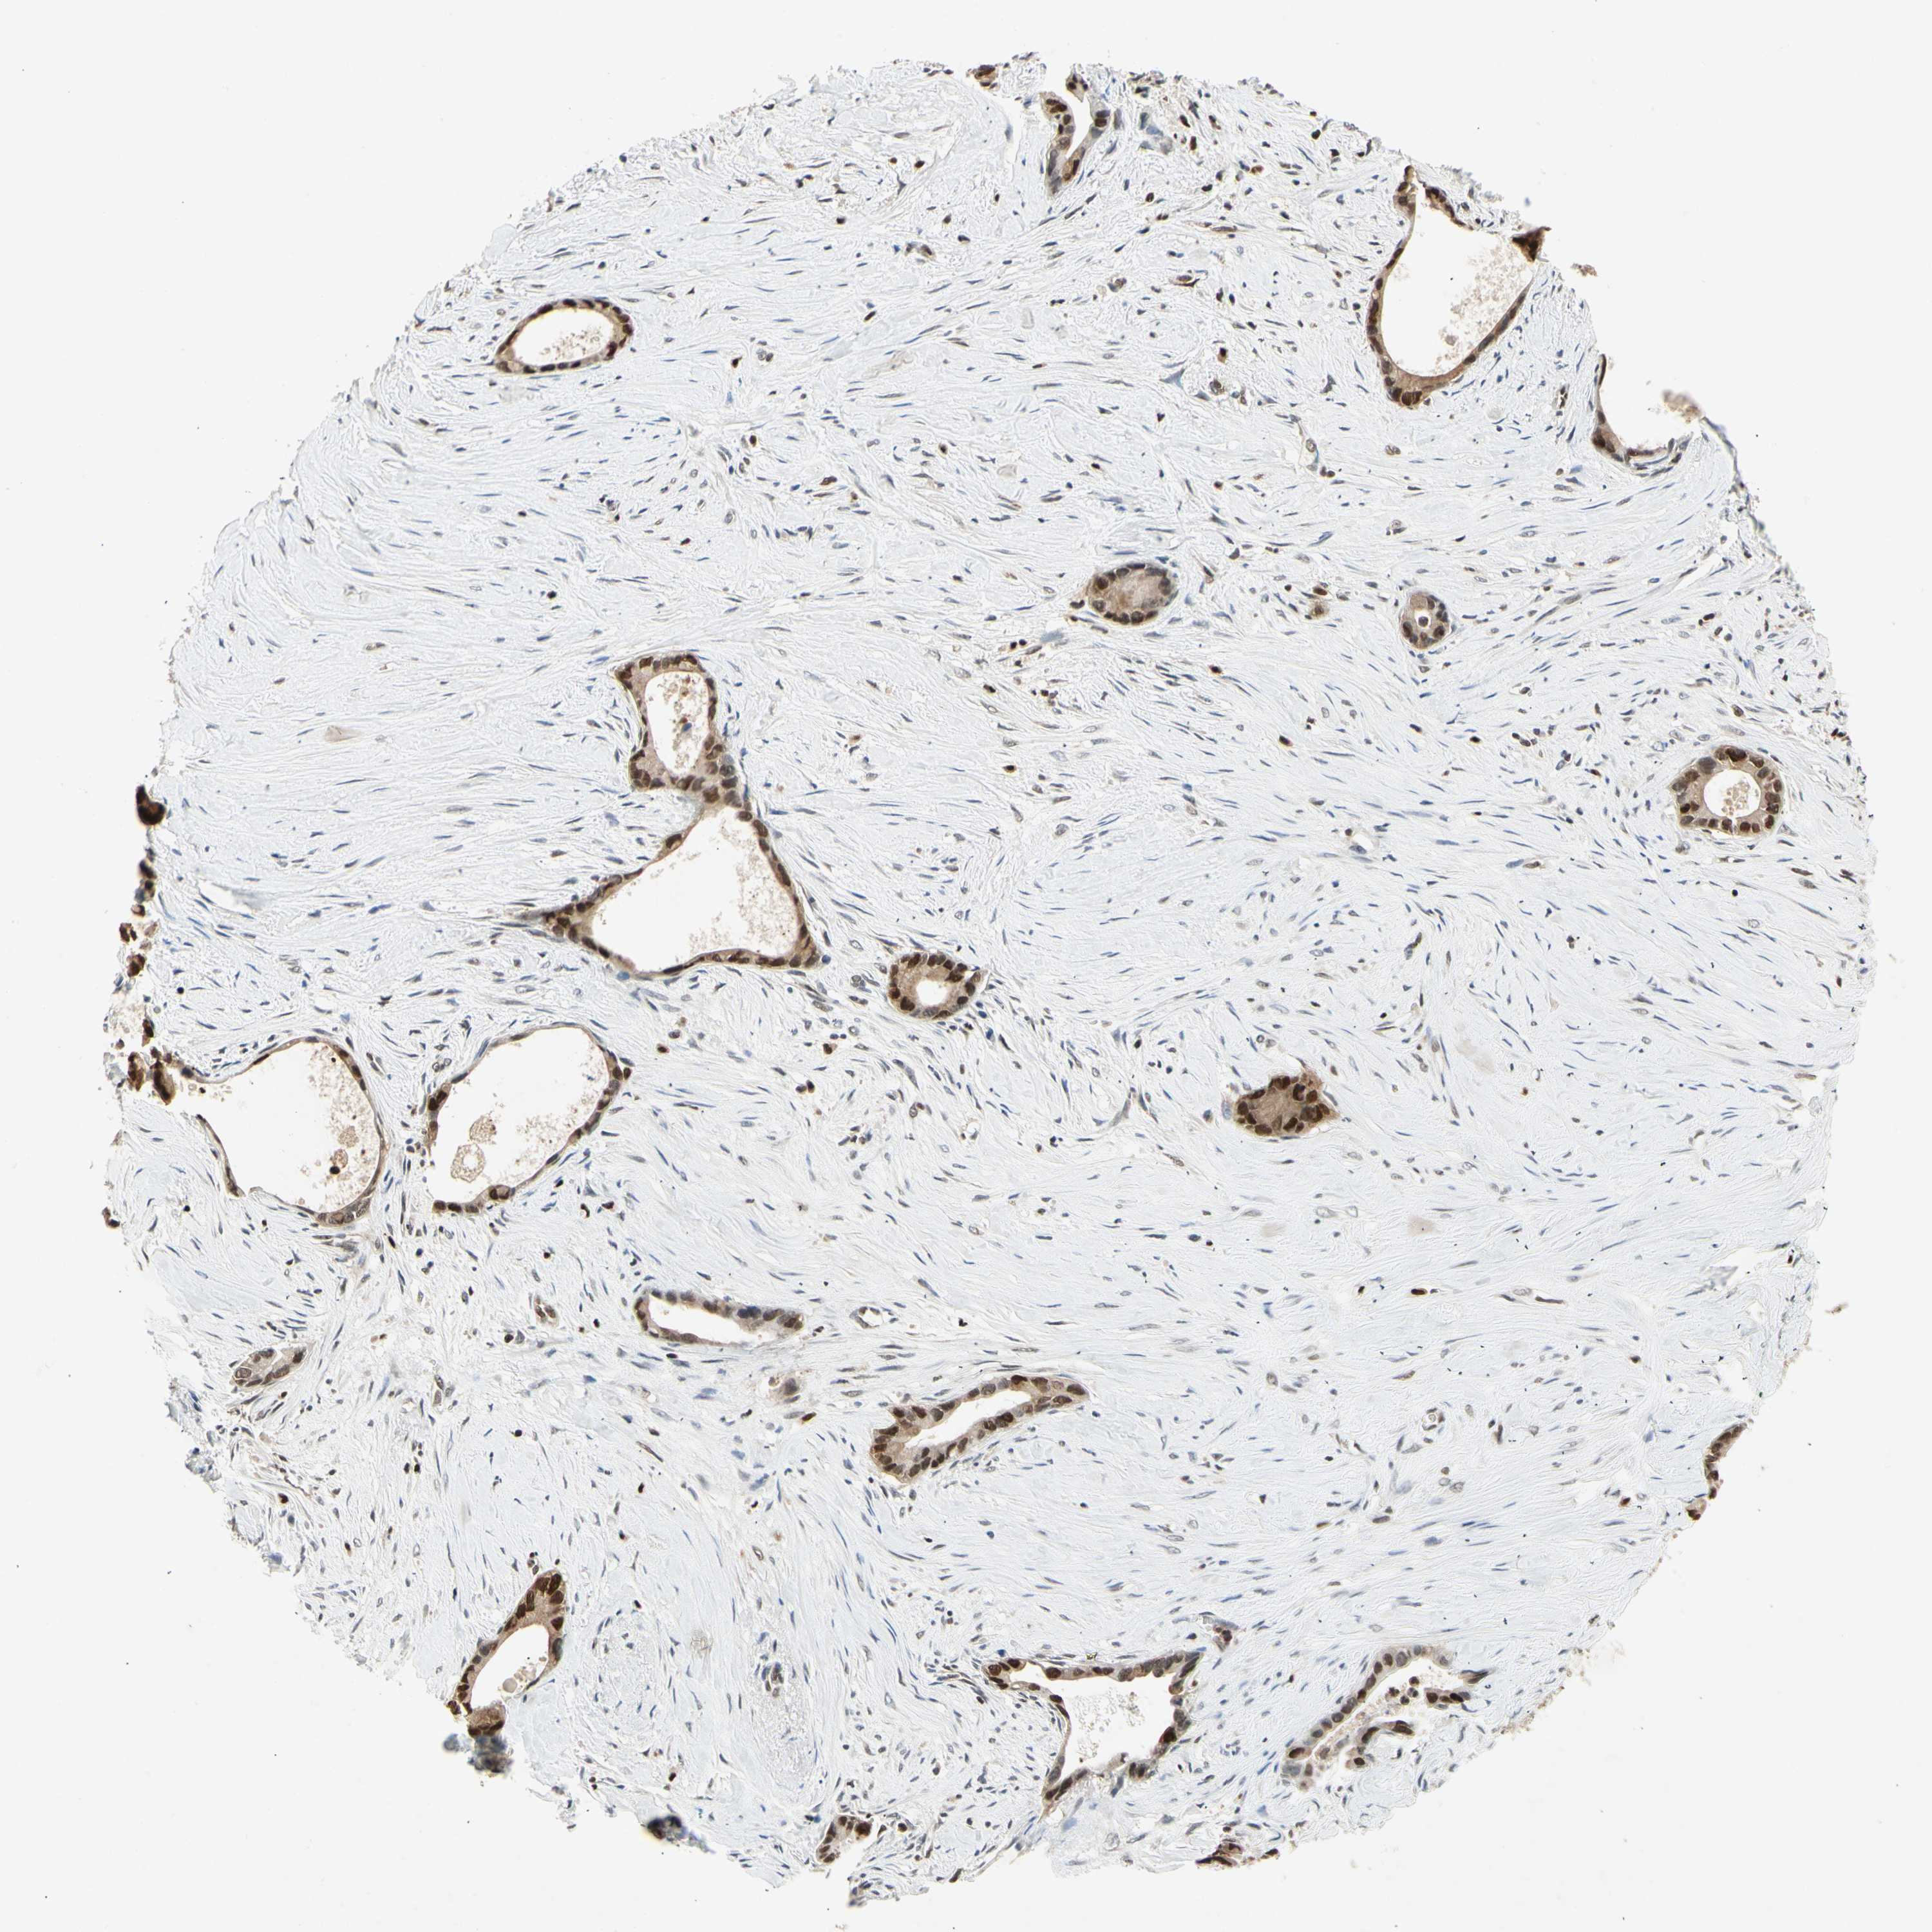

LIVER CANCER - Protein expressioni

A mouse-over function shows sample information and annotation data. Click on an image to view it in a full screen mode. Samples can be filtered based on level of antibody staining by selecting one or several of the following categories: high, medium, low and not detected. The assay and annotation is described here.

Note that samples used for immunohistochemistry by the Human Protein Atlas do not correspond to samples in the TCGA dataset.

Antibody stainingi

Antibody staining in the annotated cell types in the current human tissue is reported as not detected, low, medium, or high, based on conventional immunohistochemistry profiling in selected tissues. This score is based on the combination of the staining intensity and fraction of stained cells.

Each image is clickable and will lead to virtual microscopy that enables deeper exploration of all samples and also displays staining intensity scores, fraction scores and subcellular localization as well as patient and tissue information for each sample.

Antibody HPA001538

Antibody CAB008632

Staining

High

Medium

Low

Not detected

Intensity

Strong

Moderate

Weak

Negative

Quantity

>75%

75%-25%

<25%

None

Location

Nuclear

Cytoplasmic/membranous

Cytoplasmic/membranous,nuclear

Cholangiocarcinoma

Carcinoma, Hepatocellular, NOS